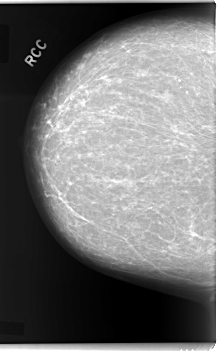

C_0084_1.RIGHT_CC

RIGHT_CC LINES 5960 PIXELS_PER_LINE 3688 BITS_PER_PIXEL 12 RESOLUTION 50 NON_OVERLAY